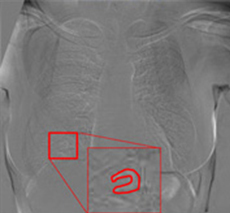

注意:赤枠は実際には表示されません。

左肺尖部に濃度の上昇がありますが、通常画像では淡い変化の為、直ぐに気づきません。読影が難しい肺尖部の鎖骨裏などでも経時差分画像で即座に変化を確認できます。